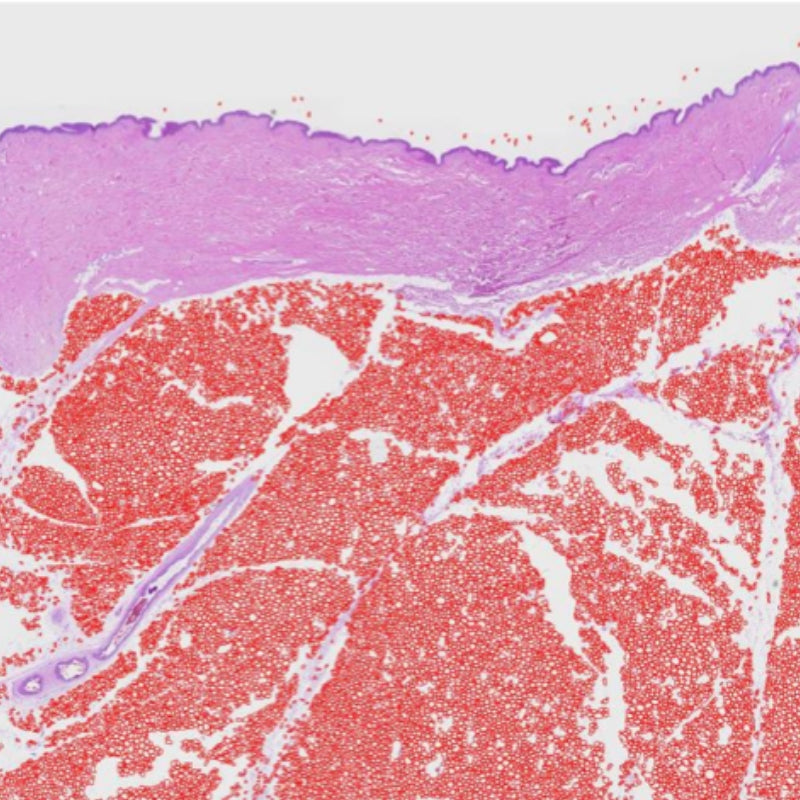

Repariert durch UV-Strahlung verursachte Hautschäden

Im Schneckenschleim enthaltene Verbindungen wie Hämocyanin, Aktin, Allantoin, Peptide und Vitamine fördern die Zellregeneration und helfen bei der Reparatur sonnenbedingter Hautschäden wie Sonnenbrand oder dem Verlust essentieller Fettsäuren, was das Erscheinungsbild trockener Haut begünstigt. Schneckenschleim hat sich aufgrund seiner erweichenden, antimikrobiellen und klebenden Eigenschaften als regenerierend erwiesen. Tatsächlich wird Schneckenschleimextrakt häufig erfolgreich zur Behandlung der Reepithelisierung von Verbrennungen bei Erwachsenen eingesetzt (Greistorfer et al. 2017; Pitt SJ et al. 2015; Tsoutsos et al. 2009).